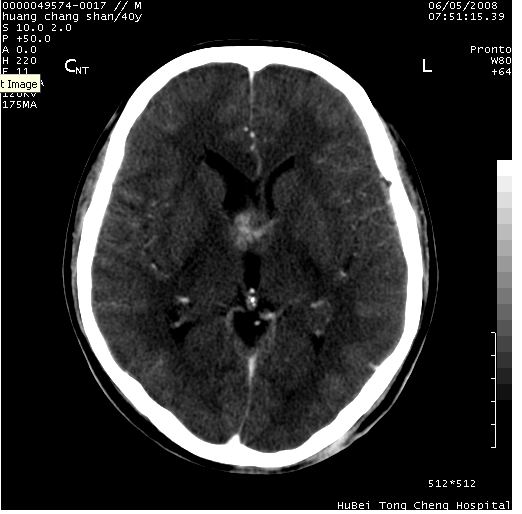

患者 m,40y。头痛,视力模糊,多饮多尿,性欲减退半年余。

行ct平扫+增强,图象如下:

鞍背无破坏和明显受压,病变明显均匀强化,边界清晰。鞍上区脑膜瘤可能性大,不除外生殖细胞瘤。

平扫病灶呈等密度,增强后强化明显,均匀一致,结合病史首先考虑:垂体瘤。脑膜瘤不支持,因为脑膜瘤平扫多为实性呈均匀高密度影像,内分泌症状多不明显,垂体内分泌素测定正常。

鞍上池肿瘤,鞍背及垂体窝形态变化不明显,病灶强化密度均匀且高度强化,考虑实性颅咽管瘤、生殖细胞瘤及脑膜瘤可能。

结合临床考虑鞍上生殖细胞瘤可能性大于脑膜瘤(增强未见脑膜围征),建议结合冠状位扫描看病灶起源及垂体窝、鞍底情况。垂体窝内未见明显软组织密度影,垂体窝未见扩大,暂不考虑垂体瘤;病灶较大,未见囊变及钙化,颅咽管瘤不支持。期待结果!

2、ct表现:肿瘤呈类圆形,均匀略高密度,无囊变,无钙化。侧脑室有扩大。

3、首先考虑:功能性垂体大腺瘤。

4、鉴别诊断:脑膜瘤,瘤体内点状钙化最具特征性,常位于鞍结节。颅咽管瘤,蛋壳样钙化,常有囊变。动脉瘤,位于鞍旁,强化与动脉一致。有时尚需与发生于鞍区的生殖细胞瘤鉴别,生殖细胞瘤钙化亦较常见。

5、友情提示:下回发现鞍区占位性病变,最好加扫冠状位,了解肿瘤与蝶鞍的关系及蝶鞍骨质的改变。